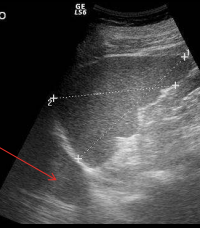

<p>En la imagen ves dos estructuras redondas dentro de un rectángulo y marcadas con flecha amarilla. Qué aspecto ecográfico tienen respecto del parénquima del bazo marcado con flecha roja</p>

En la imagen ves dos estructuras redondas dentro de un rectángulo y marcadas con flecha amarilla. Qué aspecto ecográfico tienen respecto del parénquima del bazo marcado con flecha roja

Isoecogénicas